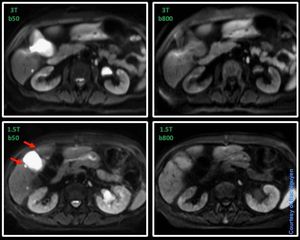

MR Liver Imaging – DWI 3T vs. 1.5T @ Siemens Skyra and Aera This is just an example between 3T and 1.5T. DWI on 3T can be more challenging compared to 1.5T due to susceptibility artifact. Take a closer look at the area of the gallbladder, the two cysts (red arrow) are not visible on 3T due to distortion. Nevertheless, a highly optimised DWI on 3T can give great results. Same patient, just different exam time.#s_mri #siemens #mri #liver_imaging #dwi